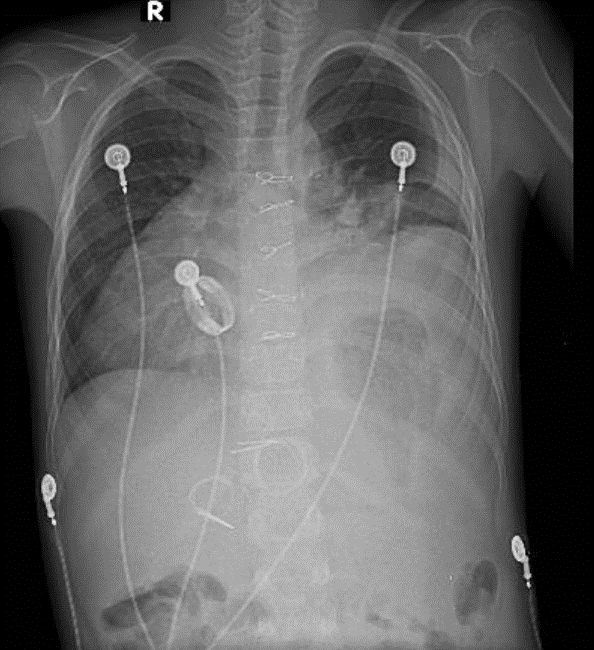

1-Thâm nhiễm phế nang thùy dưới phổi (T)=>Viêm phổi 2-Tràn dịch màng phổi (T) 3-Mỏm tim quay sang phải (đảo ngược phủ tạng) 4- val 2 lá nhân tạo 5-chỉ kim loại dọc xương ứng và các điện cực